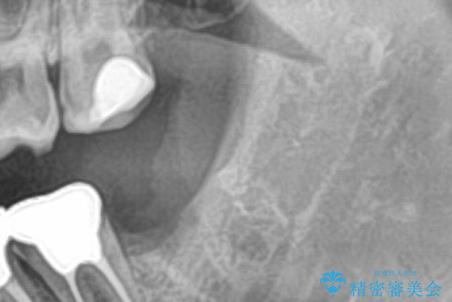

大きく歯が欠けた。 外科処置を行ったセラミック治療

歯冠長延長術をおこなったアプローチの難しい虫歯治療

左奥歯が痛い。(親知らず抜歯 ジルコニアクラウン)